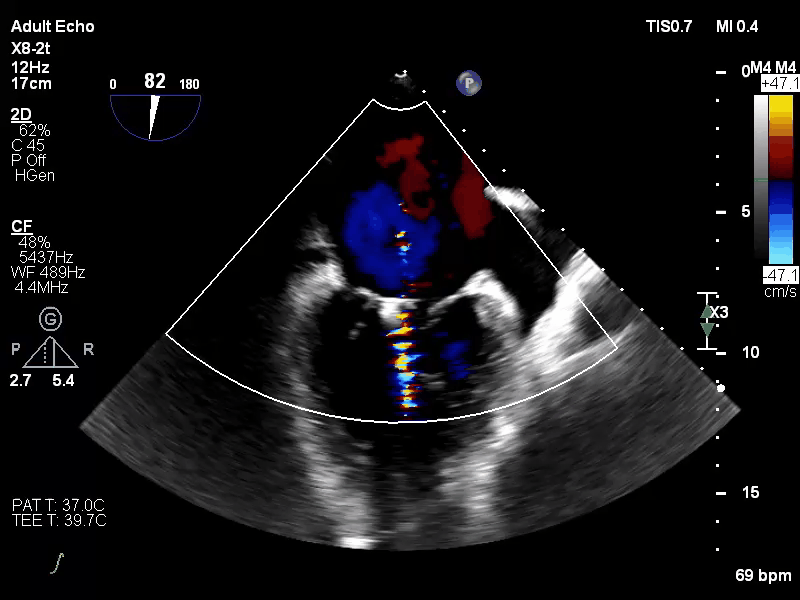

病例三

术前评估:

Carpentier II,DMR,二尖瓣P2区域腱索断裂导致极重度二尖瓣反流,心脏扩大,瓣口面积12cm²。反流束来自于2区,呈偏心性,沿前叶走行,EROA=0.51cm²,VC 0.97cm。

手术于全麻下进行,采用股静脉房间隔途径,房间隔穿刺后置入外径22F导管鞘及夹合器输送系统,在TEE引导下,将1枚长宽型号的KoKaClip®夹合器顺利植入到二尖瓣2区,夹合器位置稳定。彩色多普勒超声未见明显残余反流,肺静脉多普勒波形由反向恢复正常。多切面证实夹合组织充分,双孔化形成,遂移除器械输送系统,移除后夹合器活动度小,手术顺利完成,患者已于近日出院,出院超声复查良好。

术前

术后